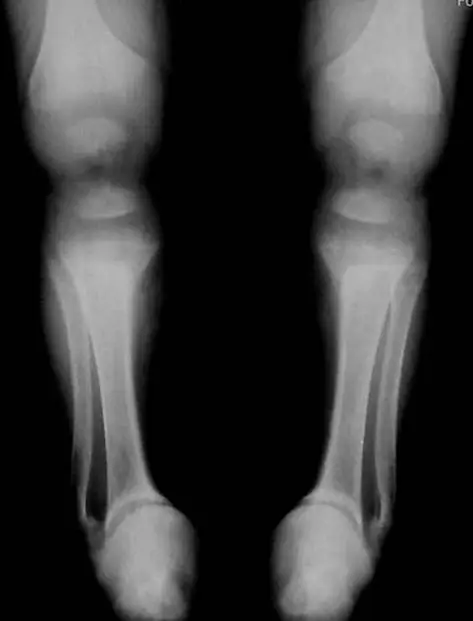

出生4個月大的早產兒,因小腸壞死長期使用靜脈營養注射,因雙側踝關節變形所照的X光影像如圖示,下列何者為最常見的診斷?

4個月大早產兒因小腸壞死長期使用全靜脈營養,罹患代謝性骨病(Metabolic bone disease),其中以佝僂症(rickets)最為常見。佝僂症係因維生素D、鈣、磷攝取或代謝異常,導致骨骼生長板礦化不良,表現在X光上為骺端擴寬、凹陷、毛邊及骨質疏鬆。

從雙側踝關節正位X光可見:

- Distal tibia、distal fibula的骺骨(metaphysis)呈現擴寬(splaying)及凹陷(cupping),邊緣不清,出現典型「毛邊」(fraying)改變。

- 骨骼整體顯示輕度骨質疏鬆,骨幹(diaphysis)骨密度降低。

- 病灶對稱且位於生長最活躍的部位(遠端脛骨、腓骨),符合佝僂症於快速生長區域以骺端改變最明顯的特點。 (radiopaedia.org)